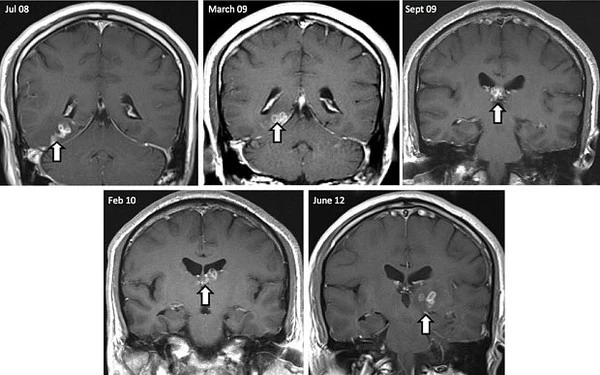

Sán dây Spirometra. Vào năm 2012, một người đàn ông Anh đã được bác sĩ chuẩn đoán là mang trong mình một cá thể sán dây Spirometra ở trong não. Trước đó vào năm 2008, người đàn ông này đã đến viện khám do bị đau đầu, co giật, trí nhớ kém và thay đổi về khứu giác tuy nhiên bác sĩ không thể xác định rõ nguyên nhân gây bệnh.

Bốn năm sau đó các bác sĩ đã vô cùng ngạc nhiên khi tìm thấy giữa các mô não là một sinh vật dài tới 10cm. Kí sinh trùng này được tìm thấy thông qua bức ảnh chụp cộng hưởng MRI. Vì chưa có thuốc điều trị hiệu quả, các bác sĩ nhanh chóng phẫu thuật để loại ký sinh trùng "ăn não" này này.